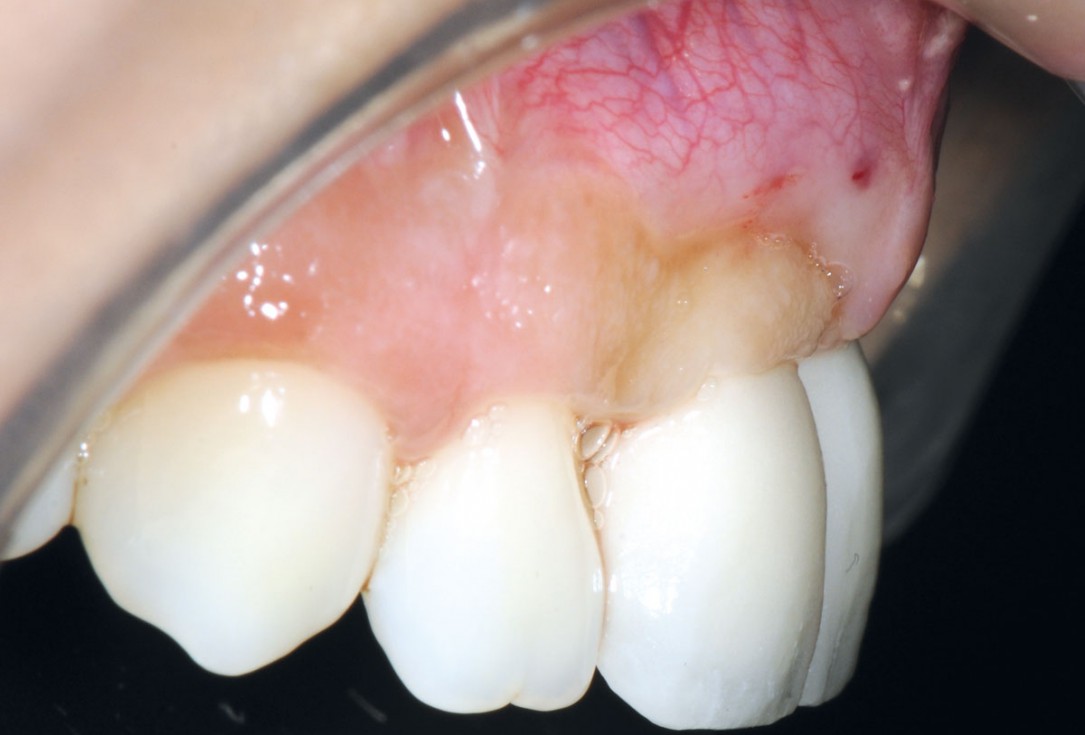

1/26 - Initially bridge retained incisorsBone augmentation in aesthetic zone with maxgraft® bonering - Dr. A. Patel

Initially bridge retained incisors